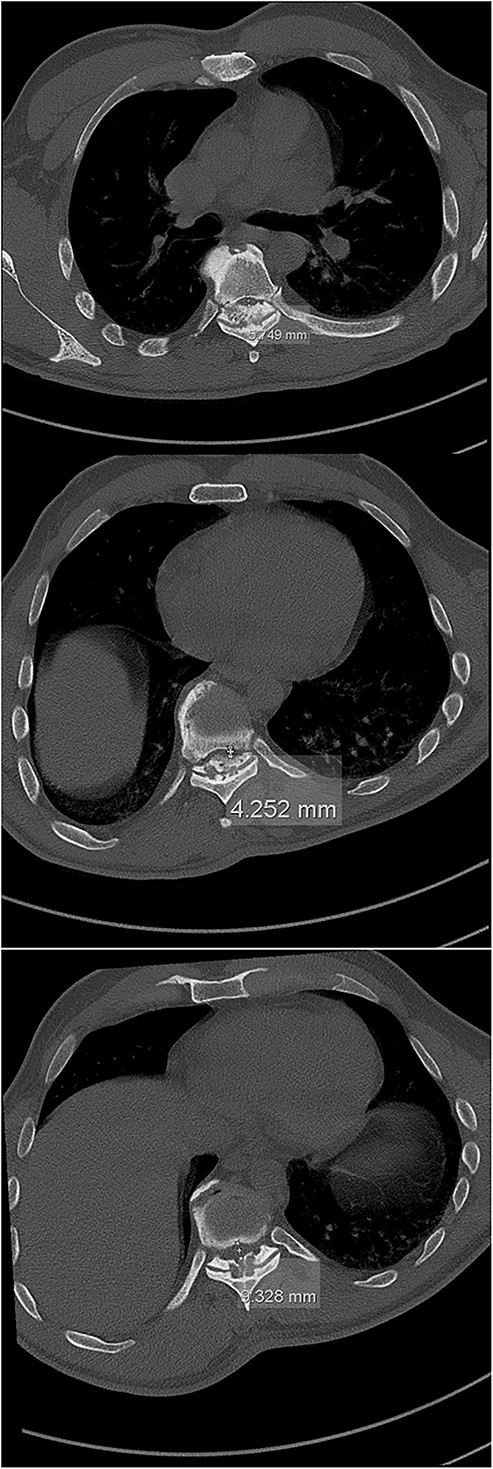

Six weeks after surgery he was transferred to a tertiary rehabilitation center, ambulating using a walker, but remained wheelchair-bound for longer distances. The postoperative pain was manageable with non-opioids. During the regular follow-ups, the paraplegia with severe spasticity persisted, without significant pain. A subsequent insertion of the intrathecal baclofen pump in a tertiary rehabilitation facility enabled the patient to manage the muscle spasms in his lower limbs, particularly during transfers from the wheelchair to bed and vice versa. The patient was able to urinate spontaneously with minimal urine retention, and no need for self-catheterisation, reporting satisfaction with the outcome of the surgery and rehabilitation, which enabled him a return to his workplace and retain a significant level of independence in everyday activities. On the final follow-up imaging, 4 years after the surgery, no significant deformity progression and no evidence of neurologic impairment were observed (Figs 4 and 5).

Final follow-up CT scan (axial views), showing adequate width of the spinal canal at Th6 (above), Th9 (middle) and Th11 (below).